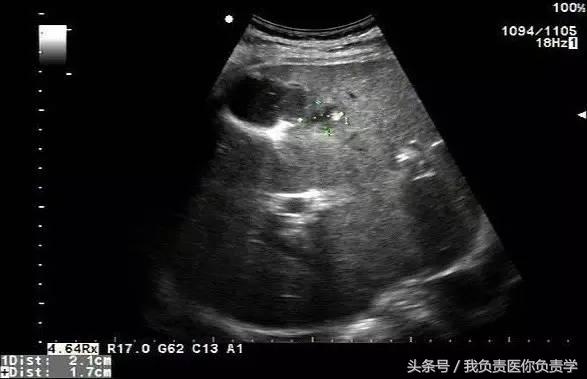

典型病例 1

患者男,64岁,因右上腹疼痛半月余就诊。查体发现右上腹部轻压痛,无发热。超声检查所见如下:

图2示于胆囊外侧可见一局限性囊性无回声区

图4和5为局部放大图像,可见胆囊与囊性回声区间可见直径约2mm的通道

超声检查考虑为胆囊炎合并胆囊穿孔,后经CT检查证实。